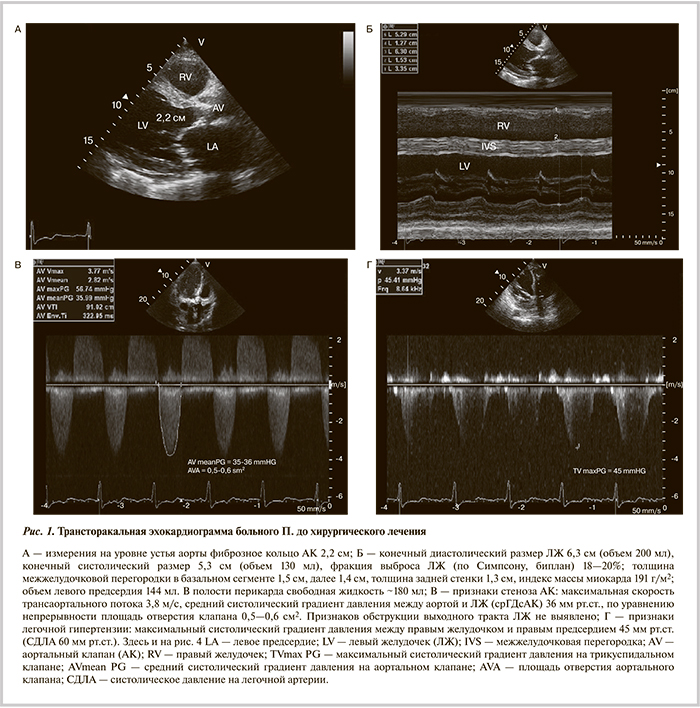

ЧДД 30 в минуту, дыхание жесткое, хрипы отсутствовали. Ритм сердечных сокращений правильный с частотой 78 уд/мин, АД 80/60 мм рт.ст. В точке аускультации АК выслушивался слабый систолический шум. Отмечались набухшие вены шеи, пульсация периферических артерий симметричная, ослабленная. Живот увеличен за счет асцита, умеренно болезненный при пальпации в правом подреберье, печень увеличена, отеки стоп и голеней. На электрокардиограмме (ЭКГ) покоя: синусовый ритм, атриовентрикулярная блокада I степени (PQ 220 мс), блокада передней ветви левой ножки пучка Гиса (QRS 110 мс), признаки гипертрофии ЛЖ. При рентгенографии легких выявлено усиление легочного рисунка за счет сосудистого и интерстициального компонентов, расширение верхнедолевых сосудов; венозный застой I—II степени; малоструктурные и расширенные корни; небольшой двусторонний плевральный выпот (гидроторакс); кардиомегалия (кардиоторакальный индекс 65%). По данным ЭхоКГ (рис. 1): критический декомпенсированный стеноз АК с кальцинозом III—IV степени и недостаточностью II степени; выраженная гипертрофия миокарда ЛЖ; увеличение размеров всех полостей сердца, преимущественно левых отделов; на фоне диффузного снижения сократимости акинезия средневерхушечных отделов переднеперегородочной стенки; нарушение диастолической функции миокарда ЛЖ по рестриктивному типу; легочная гипертензия II степени; гидроперикард; признаки повышения центрального венозного давления и малого сердечного выброса.

При суточном мониторировании ЭКГ клинически значимых нарушений ритма и проводимости сердца не зарегистрировано, средняя ЧСС 87 уд/мин. При ультразвуковом исследовании внутренних органов выявлено увеличение печени с признаками венозного застоя; умеренный выпот в плевральной и брюшной полостях, в перикарде; в парааортальной области конгломераты гипо- и изоэхогенных округлых образований (лимфатические узлы). При мультиспиральной компьютерной томографии определялся кальциноз АК с переходом на митрально-аортальный контакт; диаметр фиброзного кольца АК 2,9×2,2 см; расстояние от устья левой коронарной артерии до фиброзного кольца 1,1 см, расстояние от устья правой коронарной артерии 1,5 см; диаметр аорты на уровне синусов Вальсальвы 3,4×3,5×3,6 см; двусторонний гидроторакс; гидроперикард; внутригрудная, подмышечная, брюшная, паховая лимфаденопатия; признаки легочной гипертензии. В анализах крови гемоглобин 10—12 г/дл при нормальном уровне сывороточного железа (15 мкмоль/л), гематокрит 30%, лейкоциты в диапазоне (12—25)×109/л, лимфоидная формула, скорость оседания эритроцитов 10 мм/ч, тромбоциты 228×109/л, клиренс креатинина >60 мл/мин (формула Кокрофта—Голта), гипербилирубинемия до 37 мкмоль/л. Были начаты интенсивная диуретическая терапия, курс альбумина в связи с гипоальбуминемией (34 г/л), коррекция электролитов, продолжена терапия АСК и бисопрололом. На фоне медикаментозного лечения исчезли отеки ног, уменьшилась выраженность одышки, за 14 дней масса тела снизился на 10 кг. Однако сохранялись гипотония, синусовая тахикардия (90—95 уд/мин), тахипноэ, рентгенологические признаки легочно-артериальной гипертензии и венозного застоя легких до II степени, высокий уровень мозгового натрийуретического пептида (BNP) до 3300 пг/мл. При ЭхоКГ обращало на себя внимание значимое ухудшение гемодинамических параметров по сравнению с октябрем 2013 г. в виде снижения глобальной сократимости (ФВ ЛЖ с 38 до 20%) и уменьшения среднего градиента давления между полостью ЛЖ и аортой с 64 до 35 мм рт.ст. при площади отверстия 0,5—0,6 см2. По рекомендации гематолога, в предоперационном периоде проводилось лечение иммуноглобулином человека, в качестве антибиотика был выбран цефалоспорин третьего поколения. Непосредственно перед операцией в анализе крови лейкоциты 26×109/л, гемоглобин 12 г/дл, гематокрит 38%, тромбоциты 228×109/л.